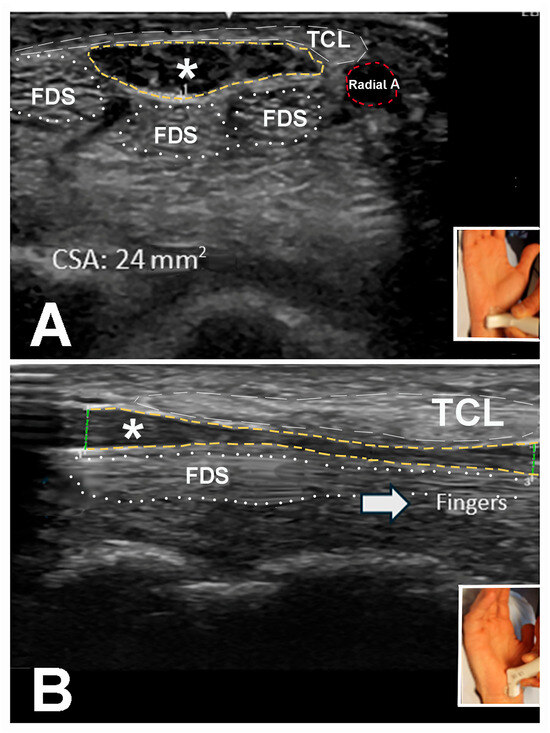

3.4. Ultrasound Studies

| Ultrasound Findings | Total Number of Hands (n = 225) |

| CT inlet/outlet CSA 10–20 mm2 | 184 (81.8%) |

| CT inlet/outlet CSA > 20 mm2 | 41 (18.2%) |

| Forearm CSA > 10 mm2 | 17 (7.6%) |

| Forearm CSA ≤ 10 mm2 | 208 (92.4%) |

| W/F ratio < 1.4 | 4 (1.8%) |

| W/F ratio 1.4–3.0 | 185 (82.2%) |

| W/F ratio > 3.0 | 36 (16.0%) |

| Diameter min/max ratio > 0.75 | 4 (1.8%) |

| Diameter min/max ratio 0.5–0.75 | 129 (57.3%) |

| Diameter min/max ratio < 0.5 | 92 (40.9%) |